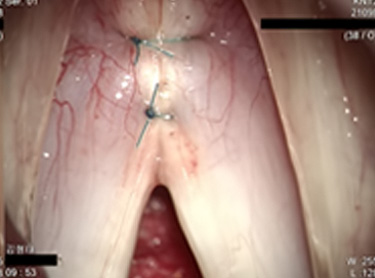

목에 절개 없이 입안으로 내시경을 통해 성대점막과 성대고유층의 1/3 지점을

제거한 후 영구적인 실을 사용하여 꿰매는 방법입니다.

수술 부위는 3~5mm로 아주 작기 때문에 미세후두기구를 사용해

양쪽 성대 근육의 앞쪽 부분을 꿰맨 후 매듭을 집니다.